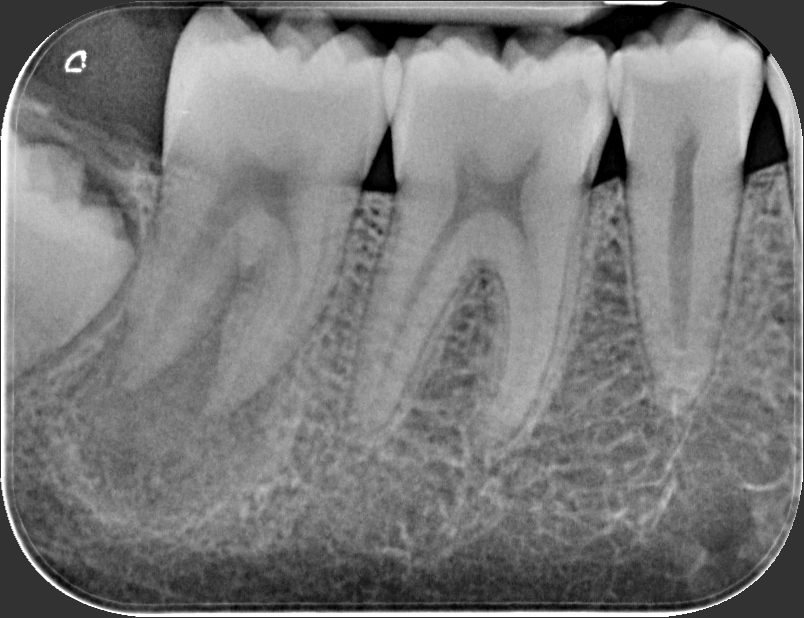

Caso clinico – trattamento ortogrado di 2° molare inferiore